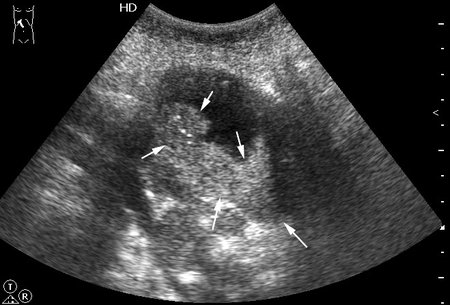

Женщина - пенсионерка. Жалобы скудные, дискомфорт в правом подреберье.